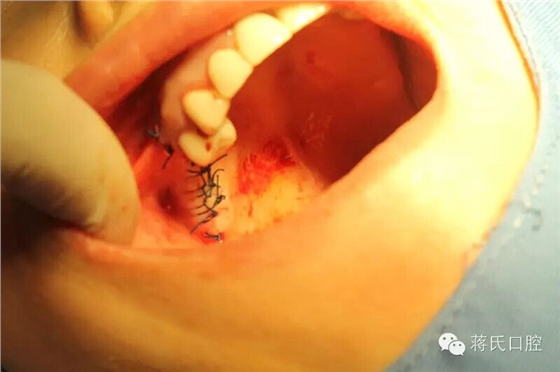

8.右側(cè)縫合后

9.左側(cè)種植前口內(nèi)